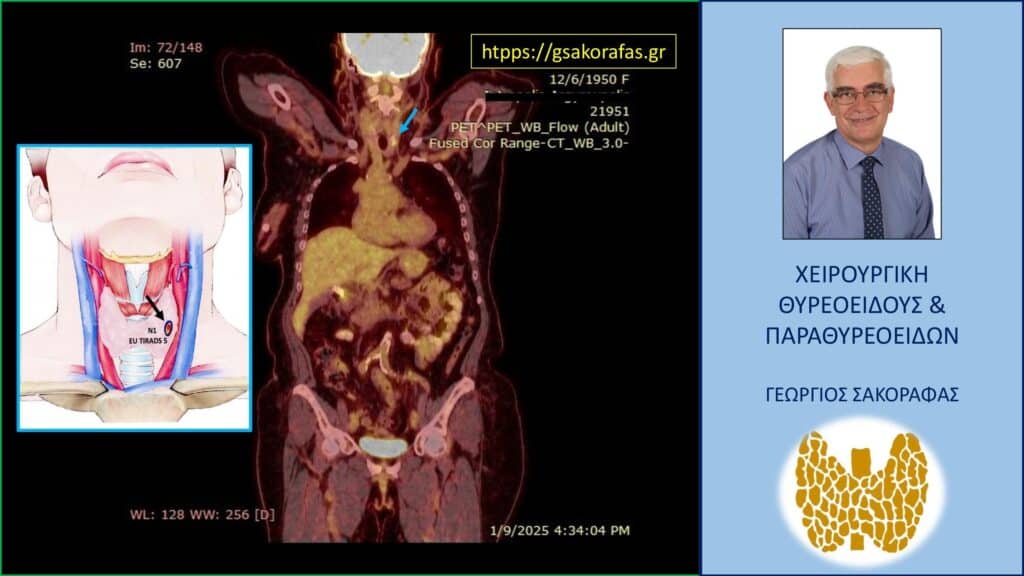

Υπερθυρεοειδισμός, Βρογχοκήλη, Όζοι Θυρεοειδούς, Καρκίνος Θυρεοειδούς

- Γιατί είμαστε σε θέση να εκτελέσουμε με ασφάλεια και αποτελεσματικότητα κάθε είδους χειρουργική επέμβαση θυρεοειδούς – παραθυρεοειδών, ακόμη και σε επιπλεγμένα (δύσκολα) περιστατικά, όπως εκτεταμένοι λεμφαδενικοί καθαρισμοί σε καρκίνο θυρεοειδούς, επεμβάσεις σε λίαν ευμεγέθεις καταδυόμενες στο μεσοθωράκιο βρογχοκήλες, υποτροπές παθήσεων θυρεοειδούς (συμπεριλαμβανομένου του καρκίνου θυρεοειδούς), υποτροπές υπερπαραθυρεοειδισμού, αδενώματα παραθυρεοειδών σε έκτοπη θέση ή λόγω υπεράριθμων παραθυρεοειδών, διάχυτη υπερπλασία παραθυρεοειδών, κλπ.